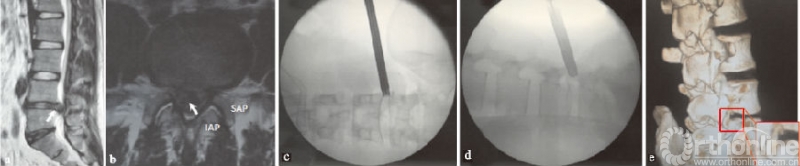

笔者认为中央型腰椎间盘突出症由于上关节突的天然阻挡(见图1a-b),要行走行神经根松解,需要做充分的关节突成形处理。中央型腰椎间盘突出症在穿刺及置入工作套管过程中,相对于其他类型的突出,椎管内压力大、神经向后或向外推挤明显,出现神经刺激症状及神经损伤的风险较高。因此,采用偏上、偏后将导杆及环锯置于上关节外侧骨面可避免直接或间接与神经根接触,这种置管方式能够减少神经刺激症状及损伤的风险,也不会破坏关节突的稳定性(见图1c-e)。

(a)(b)L4/5节段中央型突出的矢状位和横断位;(c)(d)环锯放置X线透视图;(e)术后腰椎CT三维重建图,红色方框示切除上关节突骨质范围;↖指突出椎间盘,IAP指下关节突,SAP指上关节突

图1 MRI示L4/5节段中央型椎间盘突出及环锯放置图